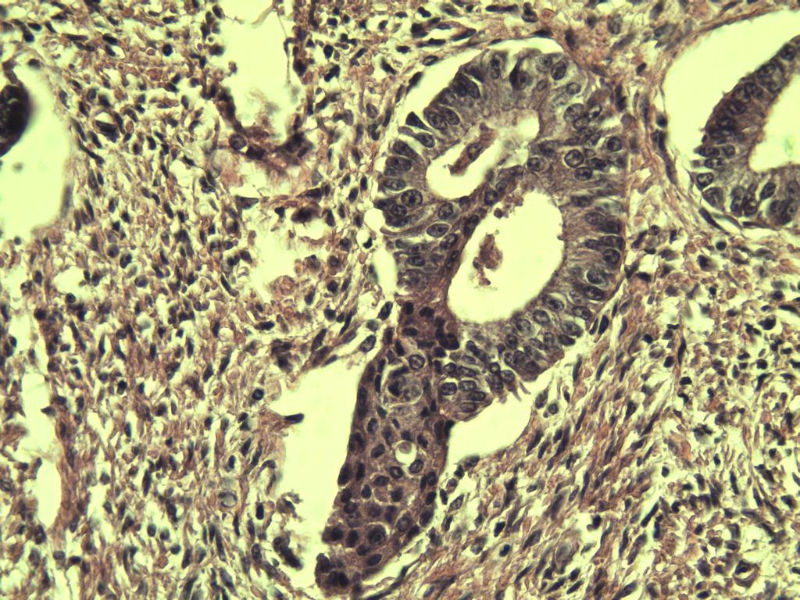

42岁 月经不规则一年 b超发现子宫肌瘤 行全子宫切除术  我取材时发现子宫颈管上段有一质地较硬区 2*1cm  请各位老师看看 是子宫内膜癌不? 谢谢了!

这是子宫颈管上段

肌层内腺体的特点:1、无内膜间质。

2、有鳞化。

3、无异型。所以应该还是个良性病变

非典型性息肉样腺肌瘤。

3.镜下特征:上皮成分由杂乱无章排列的不规则的子宫内膜型腺体构成,可以是立方形到矮柱状或假复层。显示有广泛的鳞化区域(本例图11-17均显示鳞化),表现为圆形的“桑葚”(图16-17);间质主要由平滑肌构成,且混有纤维组织。